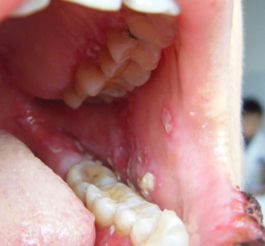

临床表现方面,结节性红斑主要表现为对称分布的皮下结节,通常位于胫前区,伴有疼痛和压痛,但一般不形成溃疡,且常伴有发热、关节痛等全身症状,但无特异性系统损害。结节多在数周内自行消退,可能复发。相比之下,白塞氏病的皮肤损害可类似结节性红斑,但常伴有其他典型特征:复发性口腔溃疡(至少每年发作3次)、生殖器溃疡、眼部病变(如葡萄膜炎)、关节炎,以及神经系统、胃肠道或血管受累的表现。白塞氏病的皮肤结节可能更易形成脓疱或溃疡,且病程慢性、反复发作。

在诊断标准上,结节性红斑主要依赖临床特征和活检(显示脂膜炎),需排除其他病因。而白塞氏病的诊断通常依据国际研究小组标准,包括复发性口腔溃疡加上至少两项其他表现(如生殖器溃疡、眼部病变、皮肤病变或针刺反应阳性)。其中,针刺反应(皮肤对轻微创伤的超敏反应)是白塞氏病的特征性表现,有助于鉴别。